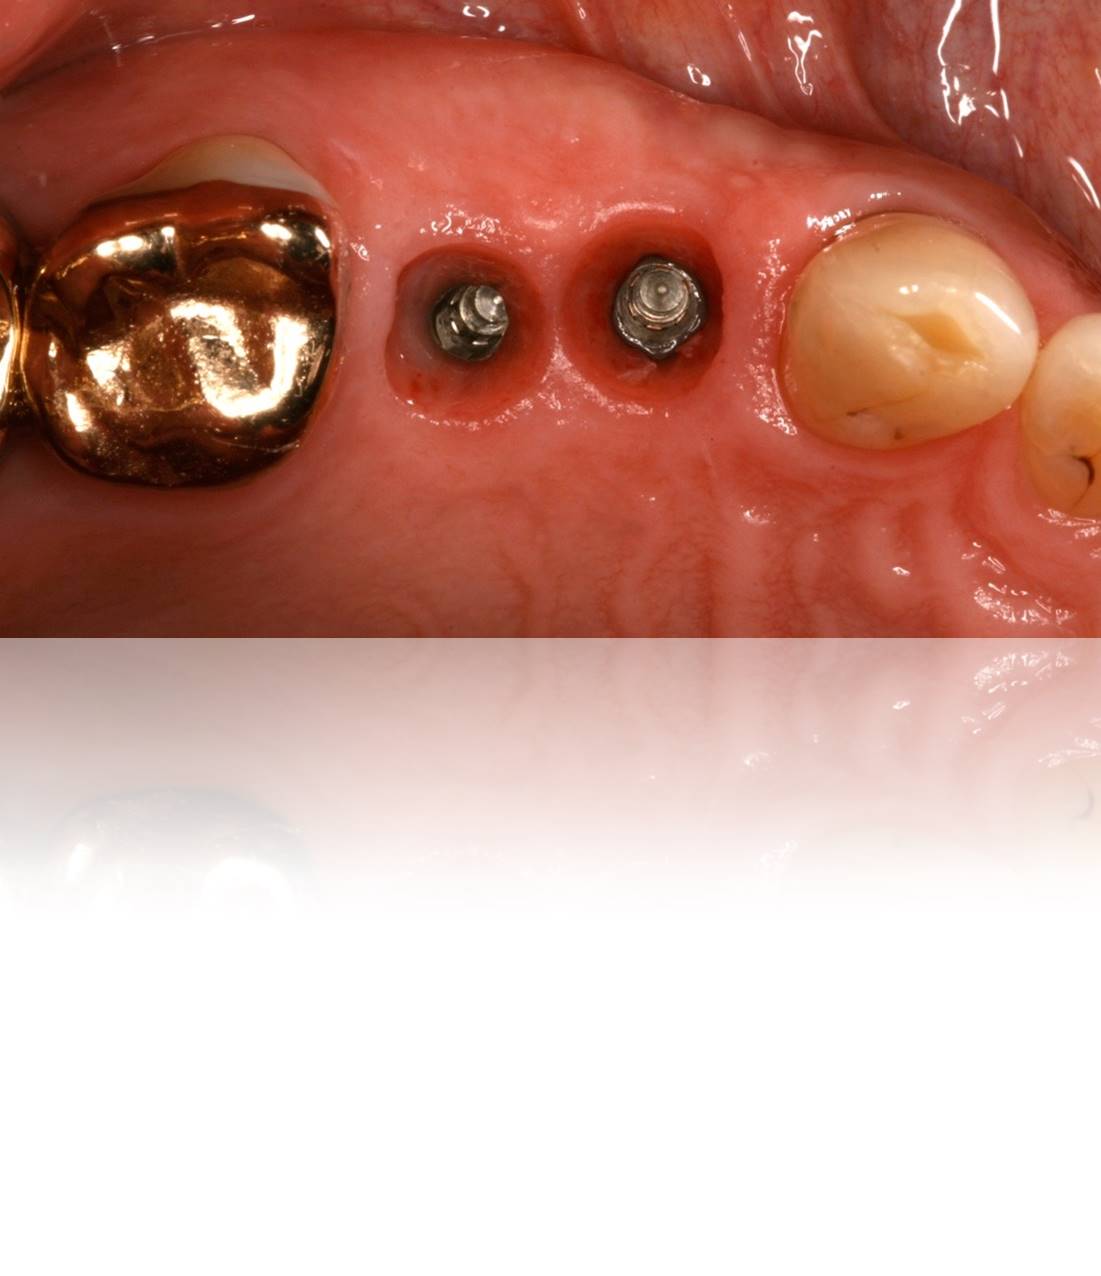

Figure 19. Close-up view of healing abutments in place for a patient who presented for implant restorations. Note this case was treated 4 years prior.

Figure 19

Figure 20. Upon removal of the healing caps, each site exhibited a deep sulcus, making “screwmentable” abutment/crown restorations ideal in order to avoid retentive cement subgingivally.

Figure 20